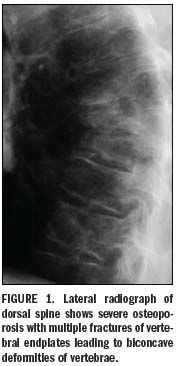

The main radiographic features of generalized osteoporosis are cortical thinning and increased radiolucency.1 Vertebral fractures are a frequent complication of osteoporosis. Although osteopenia cannot be diagnosed reliably from plain-film x-ray images, spinal radiography can help considerably when diagnosing and following up vertebral fractures (Figure 1). Vertebral height measurements can also be made on plain-film x-rays, reducing subjectivity.

Compression fractures can occur anywhere in the spine, although T4-L4 is the most common site. A vertebral fracture appears as an alteration in the shape and size of the vertebral body. A wedge is seen when the anterior vertebral body height is reduced in relation to posterior height. Reduced mid height in relation to posterior height is visualized as an endplate (mono- or biconcave), and when all heights of a vertebra are reduced in relation to the dimensions of adjacent vertebrae, this is seen as a crush, or collapse, vertebral deformity.